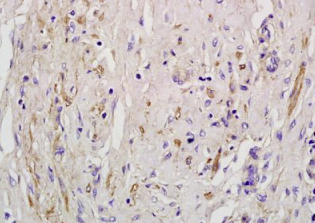

组织/细胞:人肺炎组织;4%多聚甲醛固定石蜡包埋;

抗原提取:柠檬酸缓冲液(0.01M,pH 6),15min煮沸,用3%过氧化氢阻断内源性过氧化物酶30min;37℃下阻断缓冲液(正常山羊血清)20 min;

孵育:抗at1r/agtr1多克隆抗体,未结合1:200,4℃过夜,然后与二级抗体结合,DAB染色。